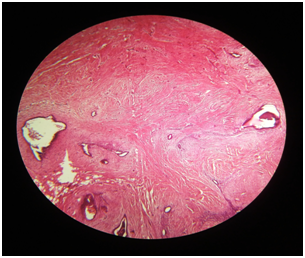

28 years old P2L2female patient reported to Gynecology department with a painful swelling at left angle of previous LSCS pfannenstiel scar for 6 years. She delivered her first Full term Alive and Healthy baby by LSCS 6 years back. She first felt pain at operated site 3 months after the surgery. It was cyclic and used to subside without any treatment. About 3 years back, she again conceived and delivered Full term, Alive and Healthy baby by LSCS. Now she presents with a tender swelling measuring 4x3x2cm at left angle of healed pfannenstiel scar. It was well circumscribed, firm and situated in subcutaneous plane. Rest of her systemic examination, vital parameters, laboratory investigations and sonographic examination were unremarkable without any evidence of pelvic endometriosios (Figure 1). Ultrasonogram (USG) of swelling showed well defined lesion measuring 2.6x1.5.x.15cm in left pelvic region at the pfannenstiel scar site which was predominantly hypoechoic with areas of hyeprechogenecity within. Based on USG findings along with clinical history, a diagnosis of Scar endomerisois was made. Patient was taken up for wide local excision of swelling with surrounding margins of 1 cm. Gross examination of excised tissue revealed irregular, grayish black fibro fatty mass with areas of congestion and hemorrhage. Histopathology examination revealed endometrial glands surrounded by endometrial stroma, embedded in fibro collagenous tissue and hemosiderin pigment at places without any evidence of malignancy (Figure 2). All histopathology findings were consistent with Scar endometriosis. On follow up period for 6 months, she did not report for any recurrence of swelling and was completely relived of her cyclic symptoms.

Figure 1 Photomicrograph showing benign endometrial glands and stroma surrounded by fibrous scar tissue consistent with Endometriosis (Hematoxylin and eosin x100).